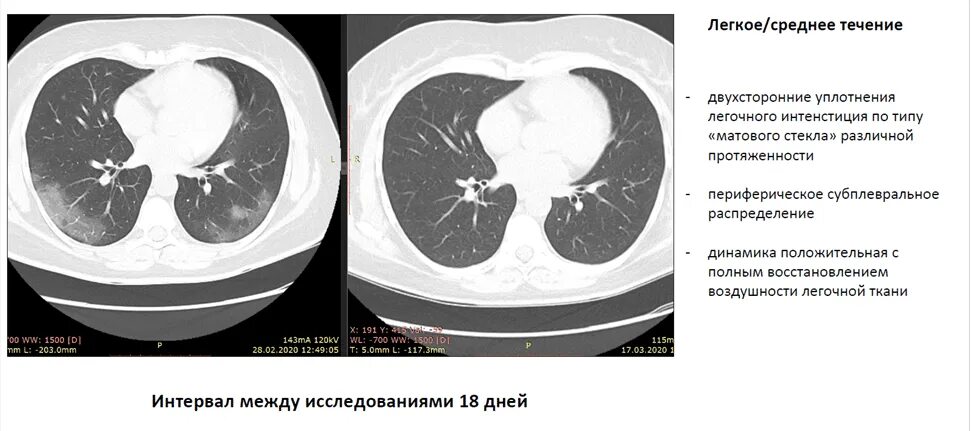

Участок уплотнения по типу матового стекла